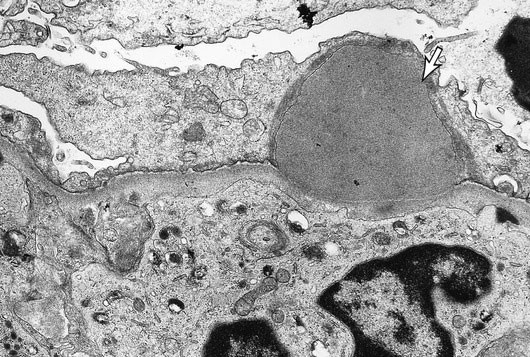

A 9-year-old child is brought to the office after experiencing facial and ocular puffiness for two days. About three weeks ago, the patient had antibiotic treatment for a rash on her leg. The temperature is 37.2 degrees Celsius (99 degrees Fahrenheit), and the blood pressure is 150/90 mm Hg. There is widespread edema but no rash on physical examination. Proteinuria and hematuria are shown by urinalysis. The following electron microscope picture represents this patient's illness process:

The area marked by the white arrow most likely represents which of the following?